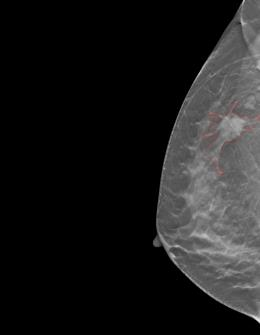

Accurately classifying malignancy of lesions detected in a screening scan plays a critical role in reducing false positives. Through extracting and analyzing a large numbers of quantitative image features, radiomics holds great potential to differentiate the malignant tumors from benign ones. Since not all radiomic features contribute to an effective classifying model, selecting an optimal feature subset is critical. This work proposes a new multi-objective based feature selection (MO-FS) algorithm that considers both sensitivity and specificity simultaneously as the objective functions during the feature selection. In MO-FS, we developed a modified entropy based termination criterion (METC) to stop the algorithm automatically rather than relying on a preset number of generations. We also designed a solution selection methodology for multi-objective learning using the evidential reasoning approach (SMOLER) to automatically select the optimal solution from the Pareto-optimal set. Furthermore, an adaptive mutation operation was developed to generate the mutation probability in MO-FS automatically. The MO-FS was evaluated for classifying lung nodule malignancy in low-dose CT and breast lesion malignancy in digital breast tomosynthesis. Compared with other commonly used feature selection methods, the experimental results for both lung nodule and breast lesion malignancy classification demonstrated that the feature set by selected MO-FS achieved better classification performance.